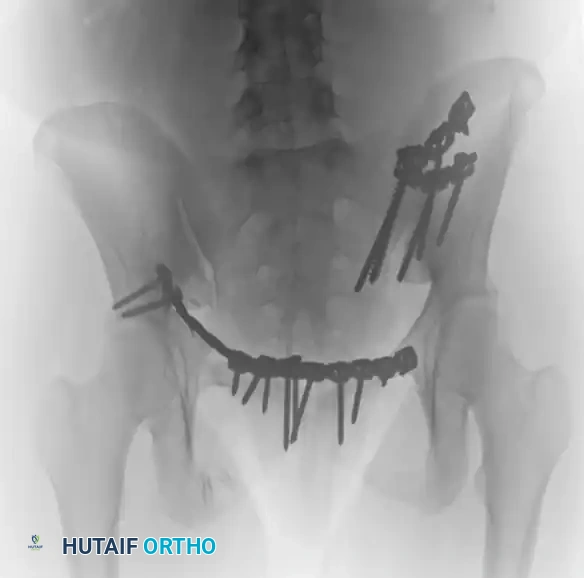

FIGURE 56-46 A-D: Young and Burgess lateral compression type III (LC III) injury with marked displacement of the right pubic ramus. Preoperative anteroposterior, inlet, outlet views, and CT scan demonstrate the severe rotational instability.